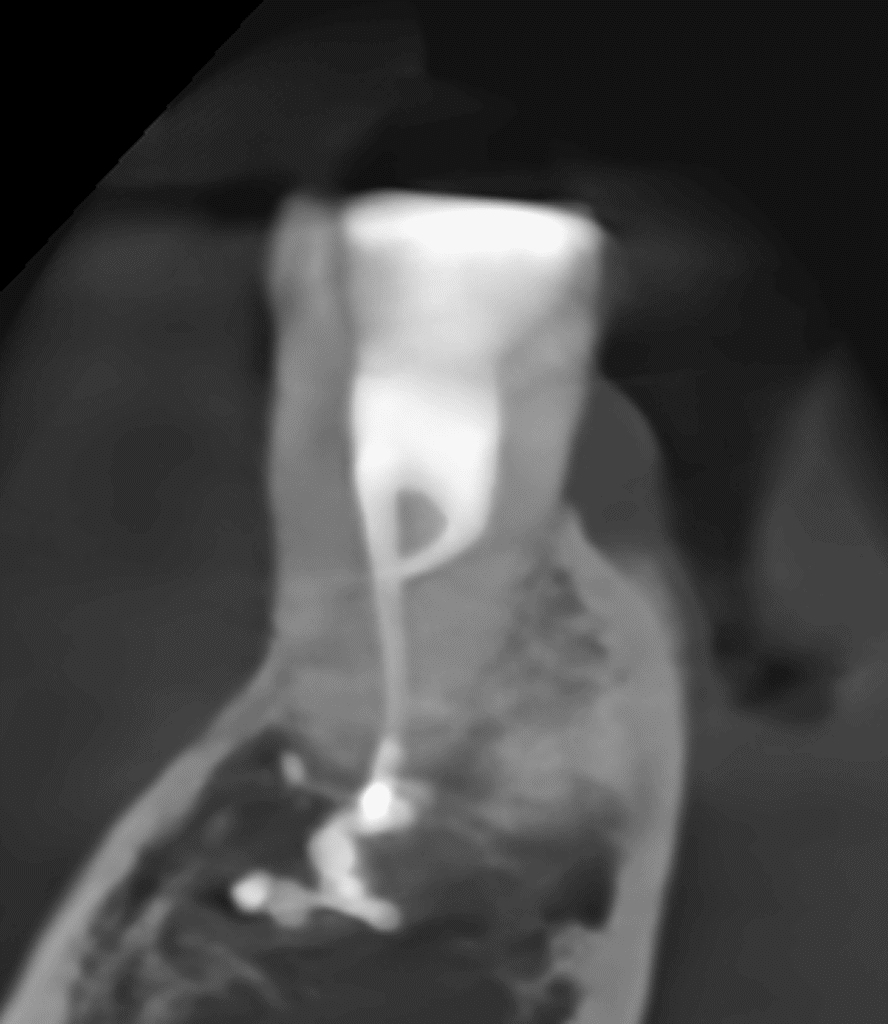

Pacjentka lat 54 trafiła do mojej kliniki skierowana z innego gabinetu celem leczenia endodontycznego zęba 46. W badaniu stwierdziłem znaczny zanik światła kanału korzeniowego. W badaniu tomograficznym stwierdziłem całkowity zanik kanału korzeniowego w strefie mezjalnej. Korzeń dystalny mimo widocznego światła kanału na CBCT, widoczne było wiele zwapnień w środkowej części kanału. Po wykonaniu dostępu endodontycznego zlokalizowałem materiał wypełniający kanał pozostawiony po poprzednim nieskutecznym leczeniu endodontycznym. Do usunięcia wykorzystałem laser 2780nm (25mJ/puls). W kolejnych etapach instrumentacji wspomaganie ultradźwiękami oczyściłem strefy mezjalną i dystalną. Instrumentacja themo-

mechaniczna polegała na zastosowaniu protokołu ciągłej chelacji wraz z użyciem lasera